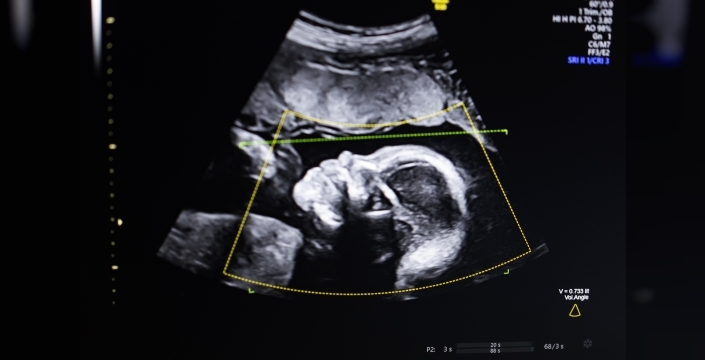

TechCrunch Disrupt Battlefield 2023'ün galibi Biotics AI, pazartesi günü yaptığı açıklamada, ultrason görüntülerindeki fetal anormalliklerin tespitine yardımcı olan yapay zeka yazılımı için FDA onayı aldığını duyurdu. Bu çığır açan ürün, kurucu CEO Robhy Bustami tarafından, kendisi gibi doktor olan annesi, kız kardeşi ve amcasının da bulunduğu bir ailede büyürken şekillendi.

Bustami, çocukluğunda sıklıkla hastanelerde vakit geçirerek annesinin ABD genelindeki anne bakımı hizmetlerine eşlik etti. UC Irvine'da kodlama öğrenip bilgisayar bilimi eğitimi aldıktan sonra, 2021 yılında Salam Khan, Chaskin Saroff ve Dr. Hisham Elgammal ile güçlerini birleştirerek Biotics AI'yi kurdu. Teknolojileri, bilgisayarlı görü yapay zekasını kullanarak "fetal ultrason kalitesi değerlendirmesi, anatomik tamamlama, otomatik raporlama ve klinik iş akışlarına sorunsuz entegrasyon" sağlıyor. Bustami, bu teknolojinin, ABD'nin yüksek gelirli ülkeler arasında en kötü gebelik öncesi sonuçlara sahip olması gerçeğiyle mücadelede yardımcı olmasını umuyor. Özellikle siyahi kadınlar, yüksek oranda anne ölüm oranlarıyla karşı karşıya kalıyor.

Bustami, gebelik öncesi ultrasonun gebelik takibinin "köşe taşı" haline geldiğini, ancak düşük kaliteli görüntülerinin yanlış teşhislere yol açabileceğini belirtti. Yapay zeka modellerini oluşturmanın zor olmadığını, 11.000'den fazla ultrason görüntüsü üzerinde eğitildiklerini ancak teknolojinin gerçek dünyada, özellikle trajik bir sonuca en yüksek risk altındaki demografik gruplarda güvenilir performans göstermesini sağlamanın en zorlu kısım olduğunu vurguladı. Sağlık hizmetlerindeki eşitsizliklerin iyi belgelendiği bir ortamda, yalnızca idealize edilmiş vakalarda değil, tüm hasta alt gruplarında tutarlı bir performans göstermenin kritik öneme sahip olduğunu ekledi. Bustami'ye göre, FDA sürecini, test ve doğrulama dahil olmak üzere tamamlamak yaklaşık üç yıl sürdü. Bu deneyim, mühendislik, ürün, klinik ve düzenleyici çalışmaların en başından itibaren sıkı bir şekilde uyumlu olmasının ne kadar kritik olduğunu kendisine ve ekibine öğretti. Ürünü, klinik doğrulamayı ve düzenleyici yolu sıralı bir şekilde değil, birlikte tasarlayarak hızlı hareket edebildiklerini söyledi. FDA onayı ile birlikte Biotics AI'nin bir sonraki odak noktası, ülke çapındaki çeşitli sağlık sistemlerinde ölçeklenmek olacak. Ayrıca fetal tıp ve üreme sağlığı için daha fazla özellik eklemeyi de planlıyor. Teknolojilerinin gücünü derinleştirmeye devam ederken hem dağıtım hem de klinik etkiyi artırma konusunda konumlandıklarını belirtti.